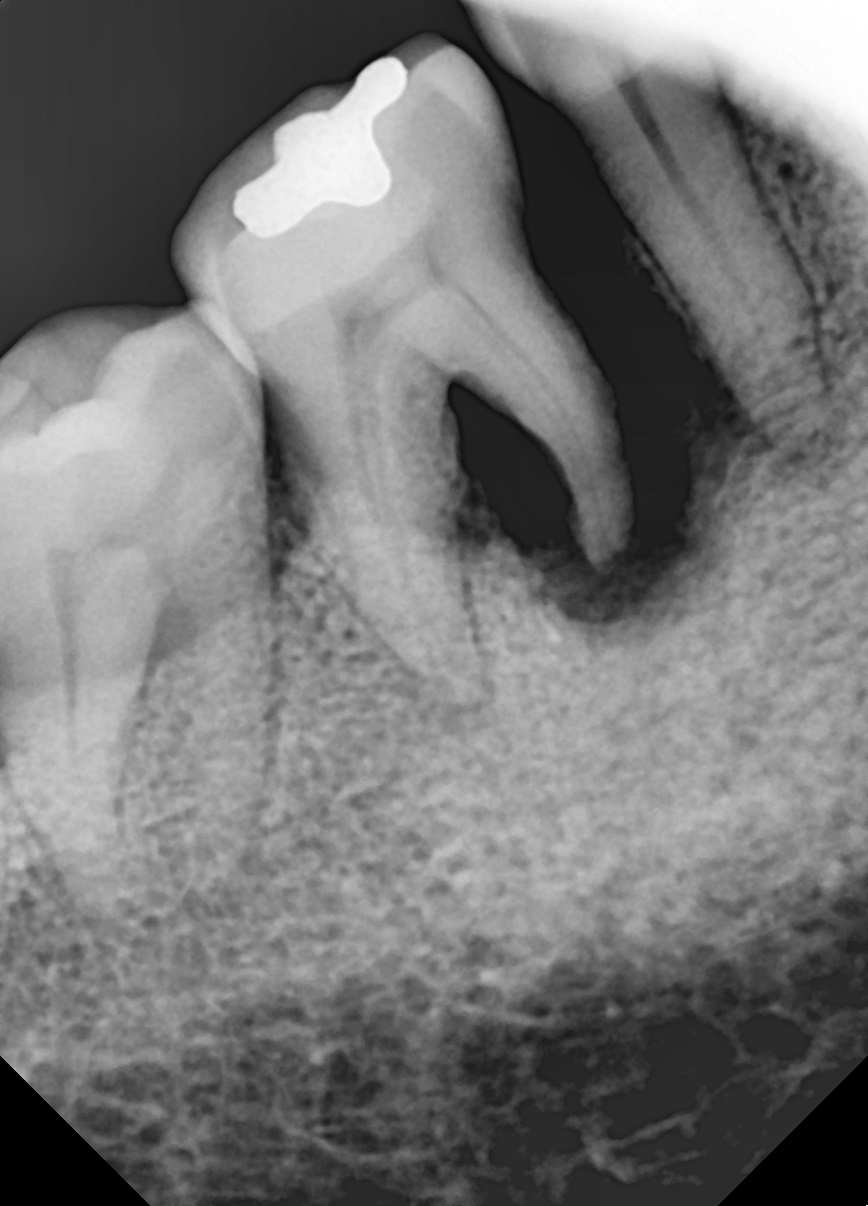

"뼈가 심하게 녹았는데

잇몸치료로 뼈가 차올랐어요"

Before

After

심한 잇몸병으로 뼈가 많이 녹은 상태

잇몸치료와 뼈이식으로 뼈 재생 후 임플란트 식립